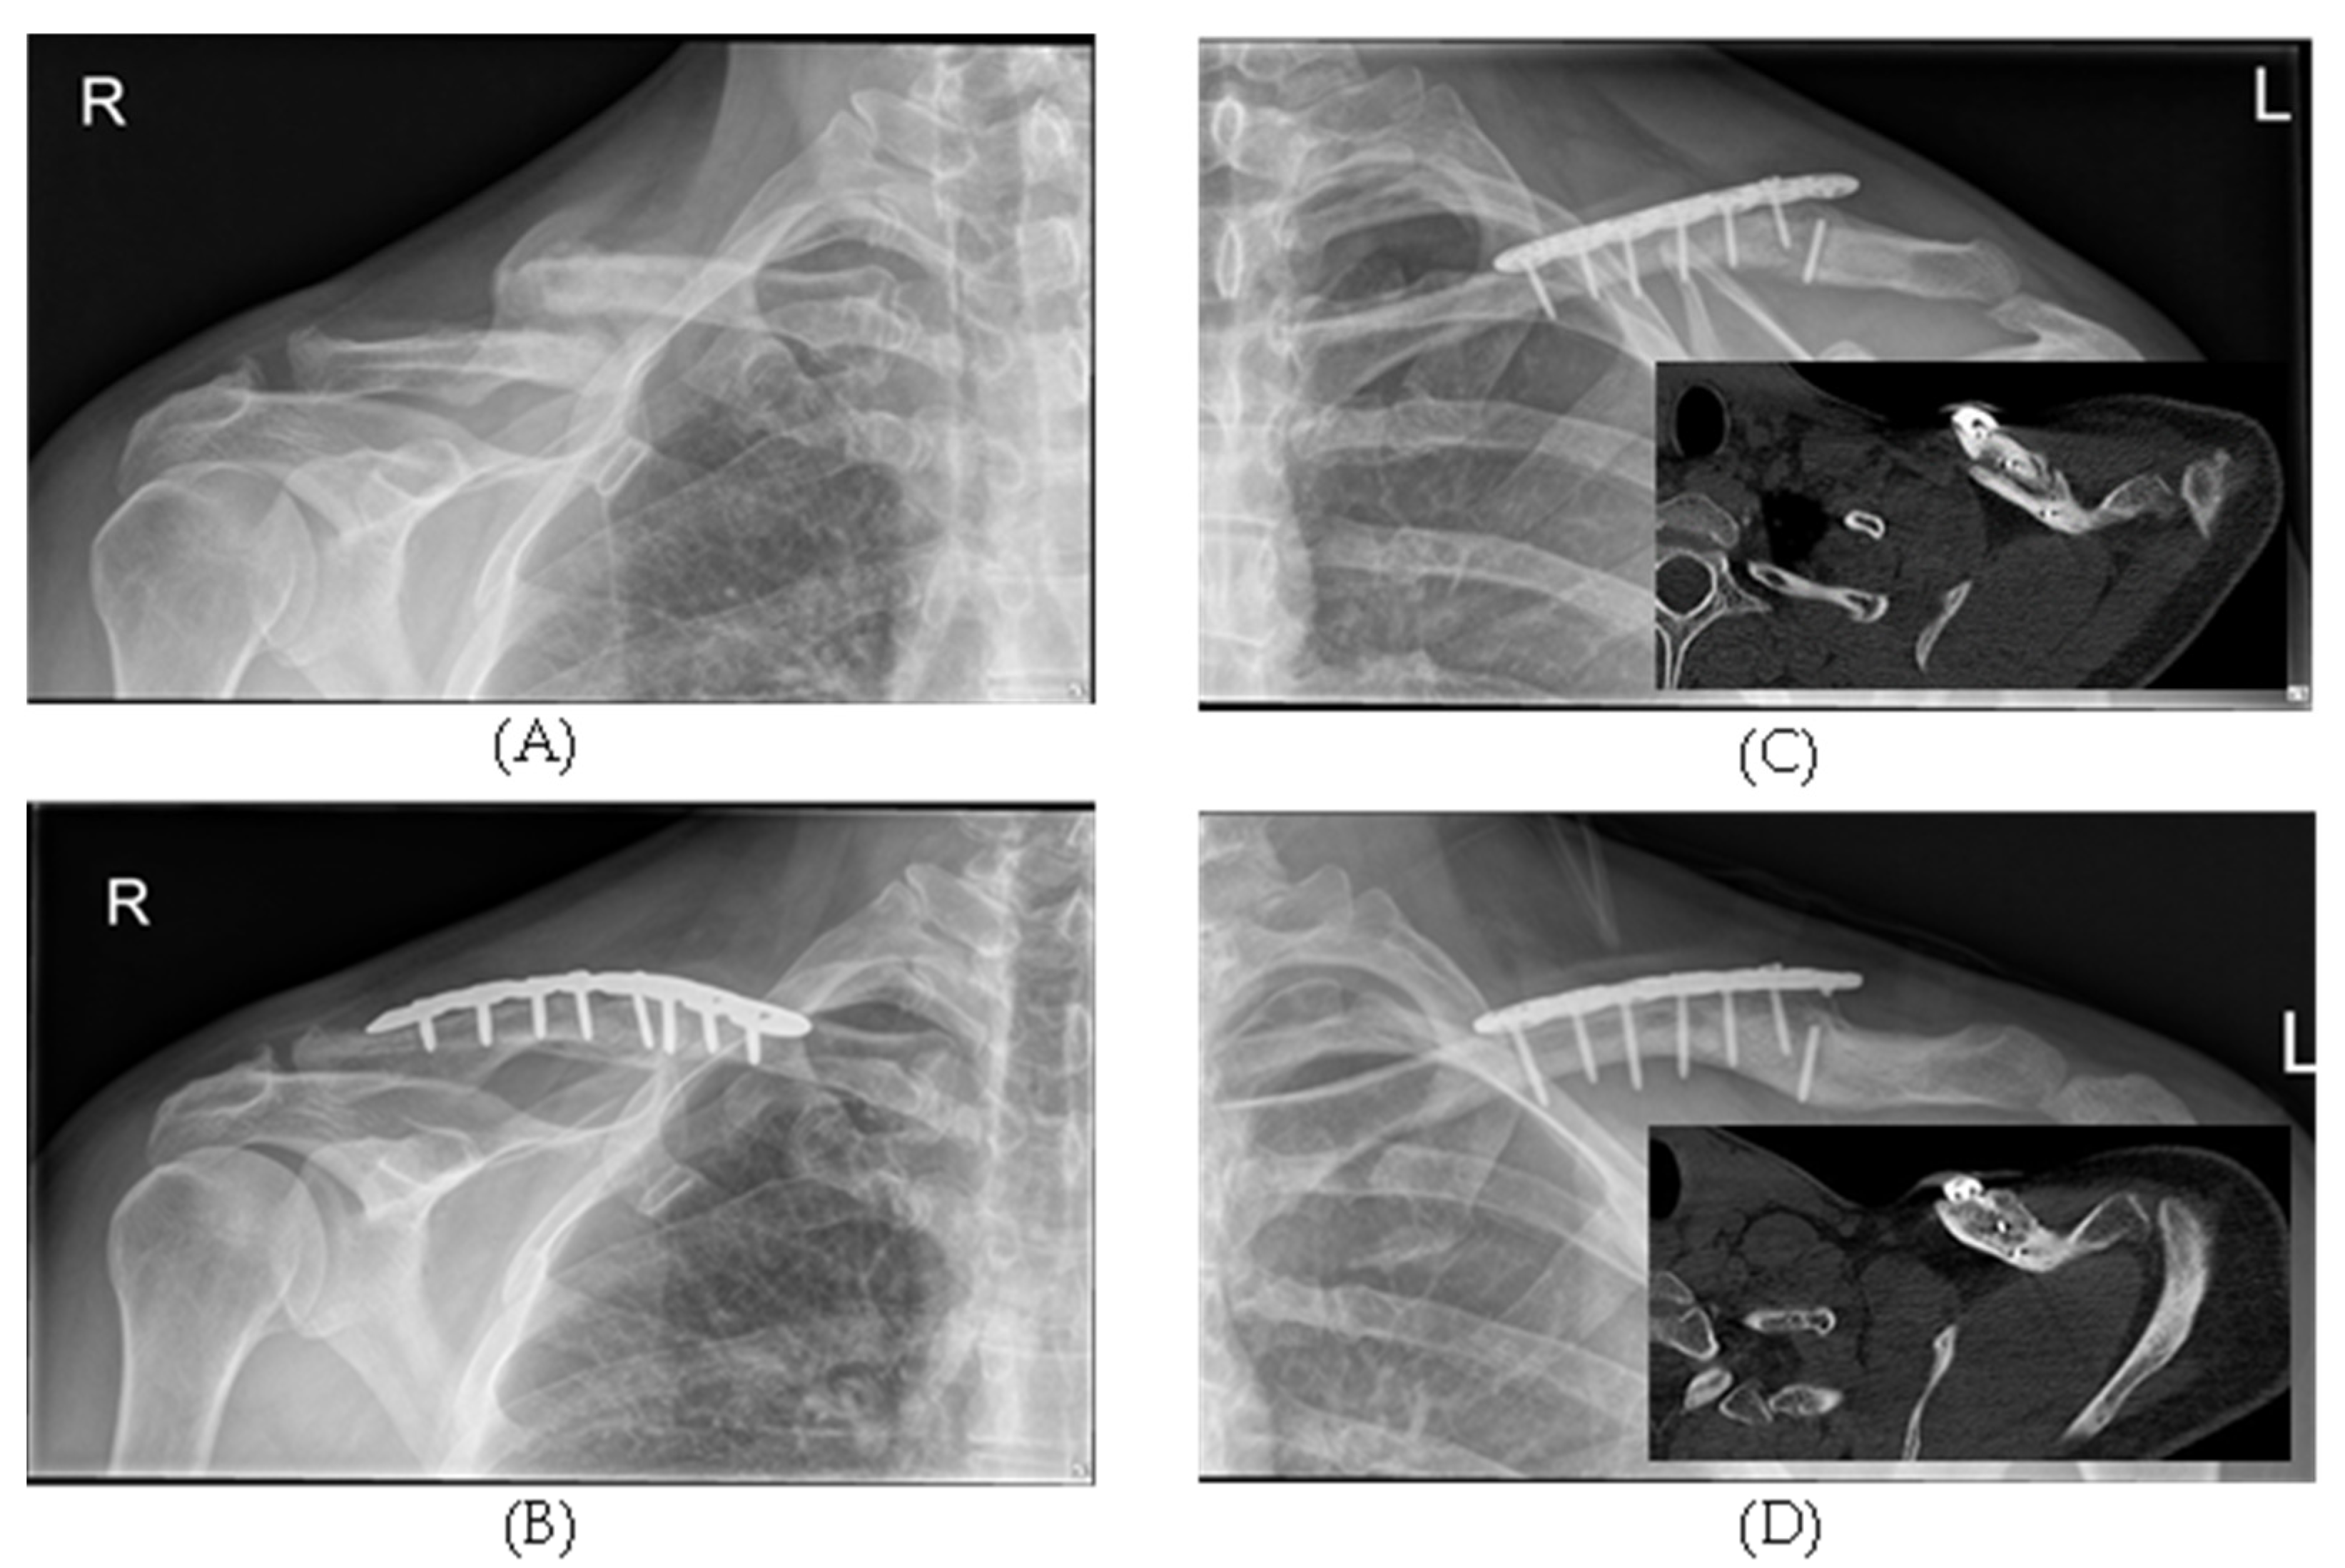

2.1.2. Surgery Group